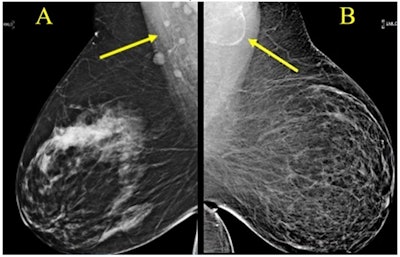

Award-winning research: Screening mammograms showed variable lymph node morphology due to ectopic fat deposition in women with obesity. Image A (above) shows normal axillary lymph nodes measuring < 1.5 cm in 63-year-old woman with a body mass index (BM) = 43.2. Image B shows a possible fat-enlarged axillary node with large fatty hilum measuring 4.2 cm in a 52-year-old woman with a BMI = 45.8. Photo courtesy of American Roentgen Ray Society.